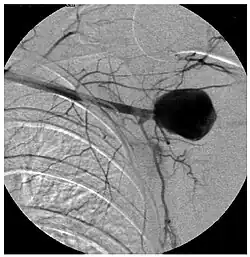

El diagnóstico debe basarse en la sospecha clínica apoyada en las técnicas de imagen, como la angiografía y la tomografía computarizada (TC), técnica de elección para la detección del aneurisma. La TC es decisiva en el diagnóstico de los aneurismas micóticos. Una vez detectados deben tratarse sin demora, pues su evolución natural es hacia la rápida expansión y rotura. La angiografía ayuda a planificar el tratamiento. La radiología intervencionista representa un papel importante en el tratamiento.[4]